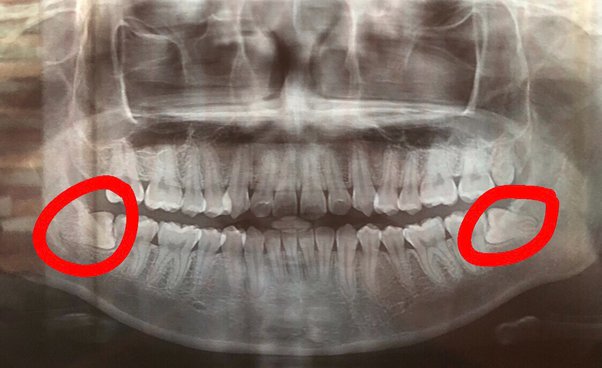

Gigi geraham bongsu merupakan gigi yang terakhir tumbuh untuk kebanyakan orang.

Gigi bongsu ialah gigi geraham terakhir yang tumbuh dan berada paling belakang.

Oleh karena itu, penting bagi kalian yang mengalami permasalahan gigi terutama pada akar gigi geraham bungsu untuk segera mencabutnya. #1 perawatan di rumah sakit; Odontektomi adalah pencabutan gigi geraham bungsu yang memerlukan tindakan bedah (ada kasus yg ga perlu dibedah, jadi tidak dihitung odontektomi).

Masa masuk check gigi doktor gigi kata gigi geraham bongsu mummy ni dah goyang. Odontektomi adalah pencabutan gigi geraham bungsu yang memerlukan tindakan bedah (ada kasus yg ga perlu dibedah, jadi tidak dihitung odontektomi). Crown sementara rm1000 ke atas.